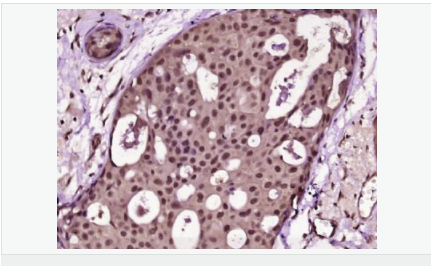

Ki67 antigen is the prototypic cell cycle related nuclear protein, expressed by proliferating cells in all phases of the active cell cycle (G1, S, G2 and M phase). It is absent in resting (G0) cells. Ki67 antibodies are useful in establishing the cell growing fraction in neoplasms (immunohistochemically quantified by determining the number of Ki67 positive cells among the total number of resting cells = Ki67 index). In neoplastic tissues the prognostic value is comparable to the tritiated thymidine labelling index. The correlation between low Ki67 index and histologically low grade tumours is strong. Ki67 is routinely used as a neuronal marker of cell cycling and proliferation.

細胞增殖標志物(Proliferation Marker)

Ki67與PCNA一樣,為細胞增殖的一種標記,在細胞凋亡中S、G2 、M期均有表達,G0期缺如。

Ki-67增殖指數(shù)高低與許多腫瘤的分化程度、浸潤、轉移以及預后密切相關,因此被廣泛作為各種惡性腫瘤的必檢項目之一。